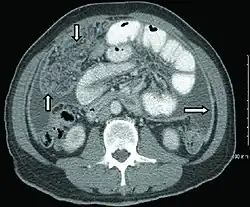

CT scan of peritoneal tuberculosis, with thickened omentum and peritoneal surfaces[1]

Abdominal infections include gastrointestinal tuberculosis (which is important to distinguish from Crohn's disease, since immunosuppressive therapy used for the latter can lead to dissemination), tuberculous peritonitis, and genitourinary tuberculosis.[4]